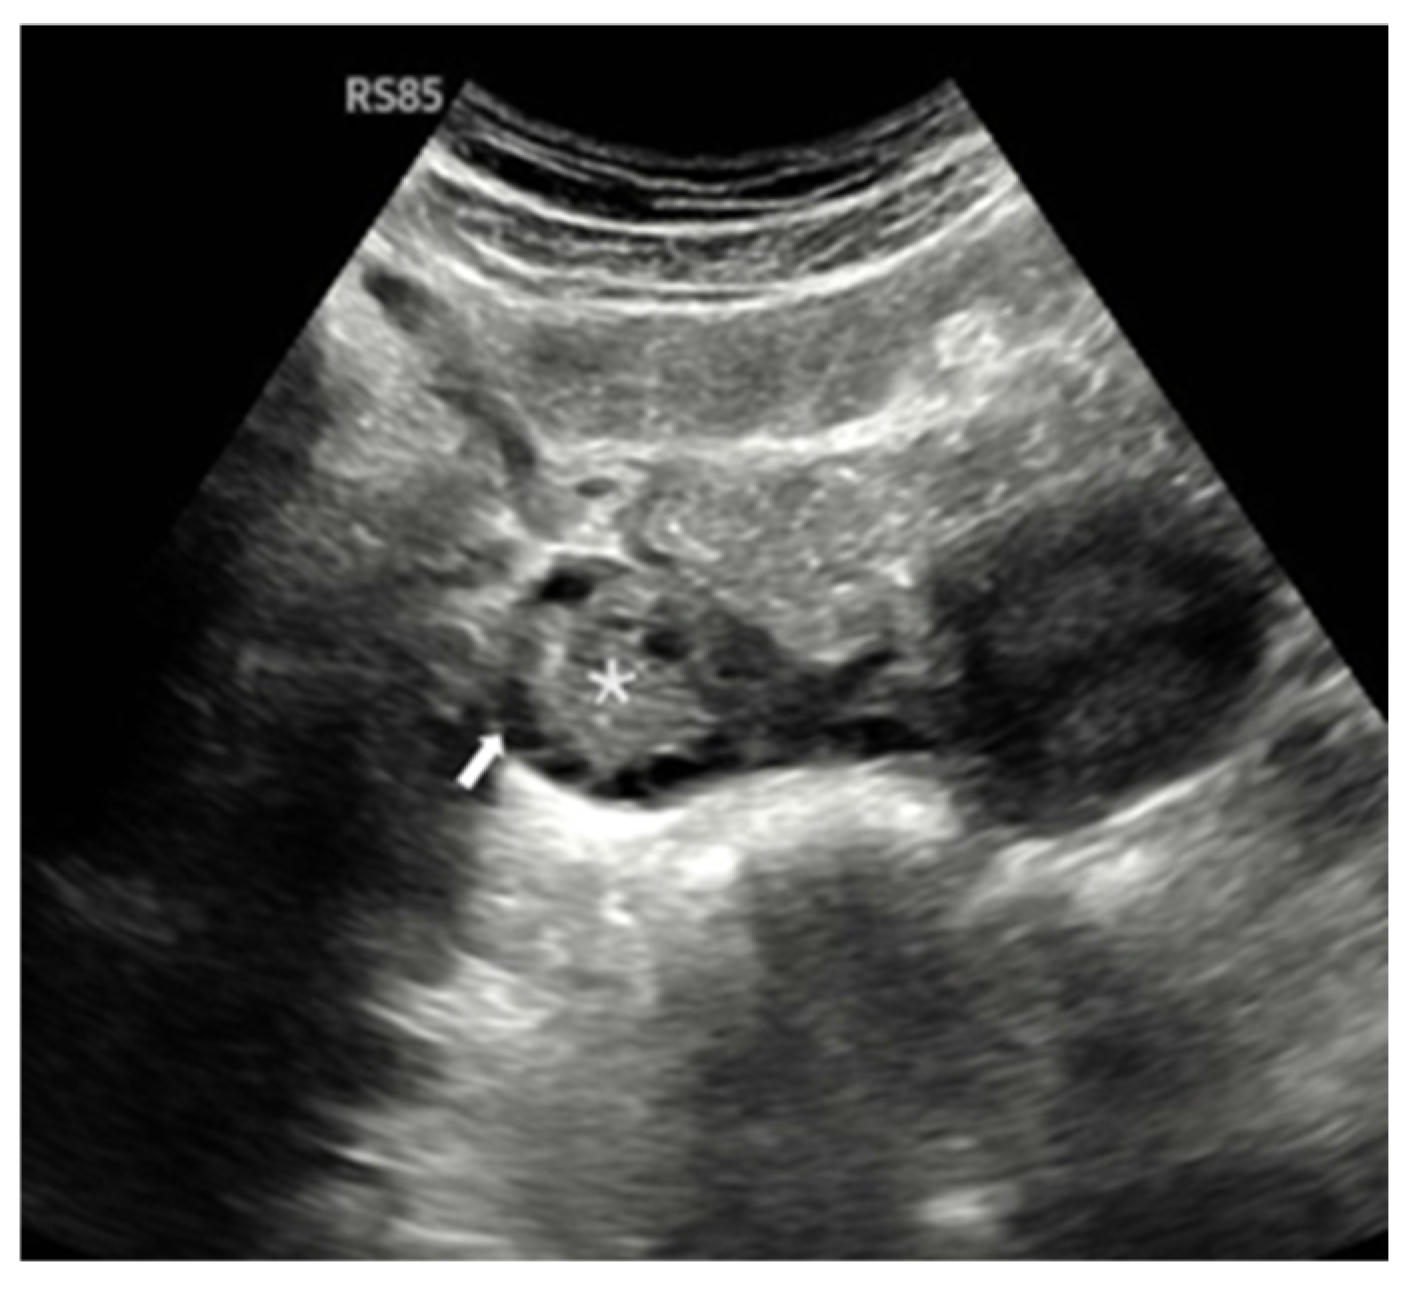

- Gray-Scale Ultrasonography (USG): A Samsung RS85 Prestige Ultrasound System (Samsung Medison) with a convex transducer (CA1-7A, 1–7 MHz) was utilized to perform gray-scale ultrasonographic assessment. The evaluation of each ovary involved a systematic examination for polycystic ovarian morphology (PCOM). This condition was characterized by either the presence of 20 or more follicles with diameters ranging from 2 to 9 mm, or an ovarian volume greater than 10 cm3.

- Doppler Examination (MV-Flow, MVI): Ovarian stromal vascularity was evaluated using the same ultrasound equipment and transducer (Samsung RS85 Prestige with CA1-7A, 1–7 MHz). MV-Flow Doppler imaging was performed consistently in the longitudinal plane to maintain anatomical standardization. Cine-loop clips of at least 3 s duration were captured and stored. For vascularity index measurements, the optimal frame demonstrating clear vascular flow was selected from the stored cine-loop clips. In the ovarian stroma, three circular regions of interest (ROIs) were centrally positioned. These ROIs, each with a fixed 5 mm diameter, were carefully selected to exclude dominant follicles and peripheral vascular structures. The ROI dimensions and MV-Flow Doppler imaging parameters, including pulse repetition frequency (PRF), gain, and wall filter, were maintained consistently throughout the duration of the study.